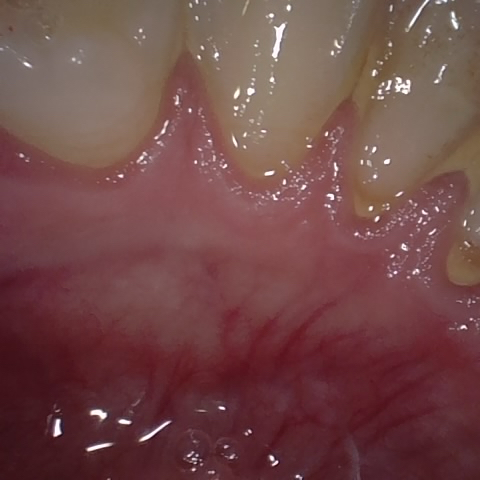

Annotated as "Good"

Original Image Rendering Image